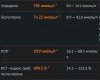

ШикТест энантат PL 125мг 1 раз в 4 дня.

Анализ после 4ой инъекции через 24 часа.